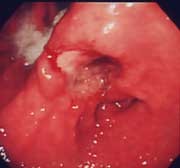

胃潰瘍:

心窩部痛、食欲不振、黒色便を訴えて来院。内視鏡検査を施行すると類円形の活動期の潰瘍を認めました。良性の潰瘍で内服治療で十分に治癒します。現在、潰瘍の原因はピロリ菌であるされ、潰瘍の治療としてピロリ菌をやっつける(除菌)ことが認められています。潰瘍を何度も繰り返している方は、是非除菌療法を考慮してください。